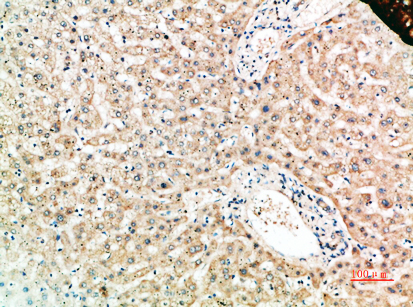

分类: 科研抗体货号: P23523别名: A1BG; Alpha-1B-glycoprotein; Alpha-1-B glycoprotein应用: WB,IHC反应种属: Human